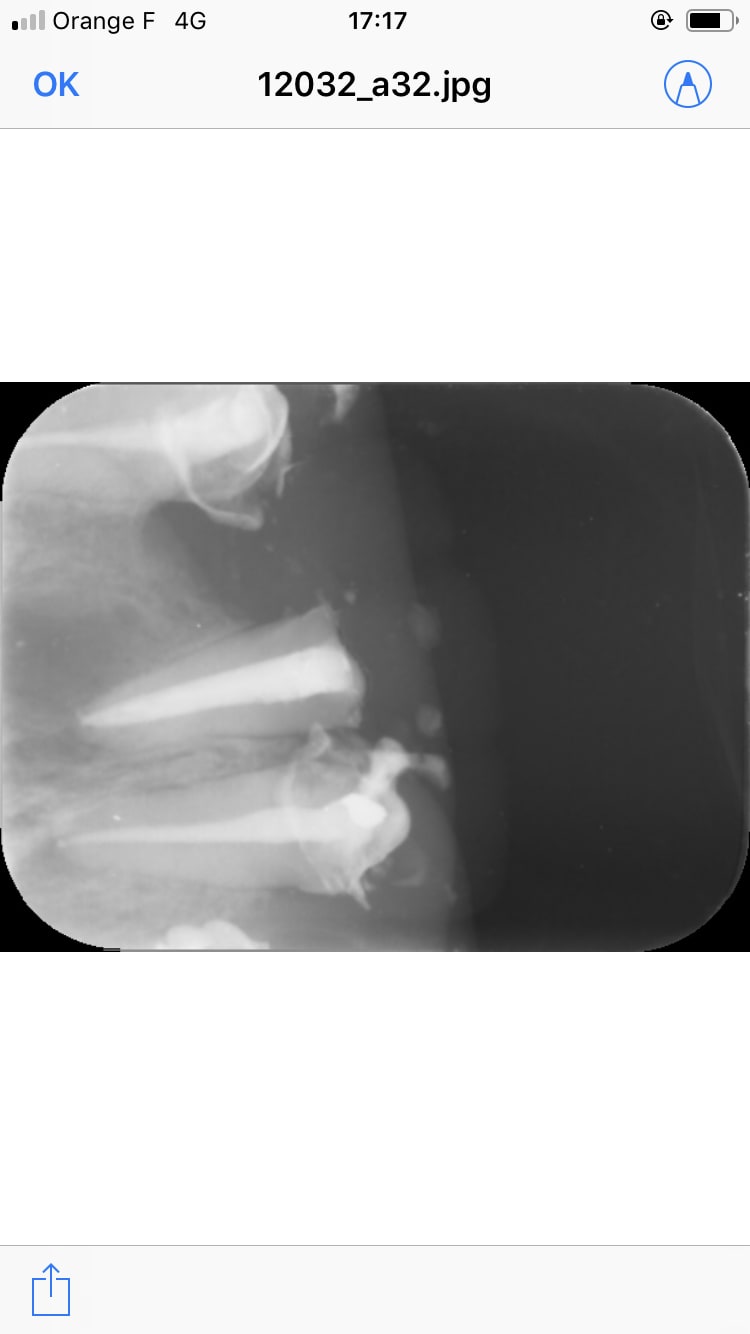

Il est où lachmar ? Cas qui a été traité par une roumaine. Il y avait un bridge que j’ai démonté avec une merde sous chaque dent.

J’ai essayé de conserver et retraiter 11 et 21 , j’attends que ça cicatrise. À la mandibule c’est pareil y a 4 dents manquantes. Plan de traitement 1 implant par dent manquante. Et chaque dents en bouche à retraiter.

La question est la suivante : est ce que je tente la conservation de la 6 avec le lentulo cassé ou je ne me casse pas le tronc et j’extrais ? As tu réussi à conserver des dents avec un lentulo cassé au delà de l’apex ?

Enlaye va rappliquer avec son extraction implantation immédiate :) , je ne peux pas le faire car le patient a déjà eu suffisamment de merdes en bouche. Faudrait pas rajouter une boulette de plus au tableau.

Photo bridge démonté

11 21 avant traitement

11 21 juste après retraitement

Radio de la 6 avec le lentulo

> Photo bridge démonté

> 11 21 avant traitement

> 11 21 juste après retraitement

> Radio de la 6 avec le lentulo

cher junior

ce cas aurait pu être traité par n'importe quel dentiste malhonnete

pour le lentulo chirurgie apicale et obturation retrograde